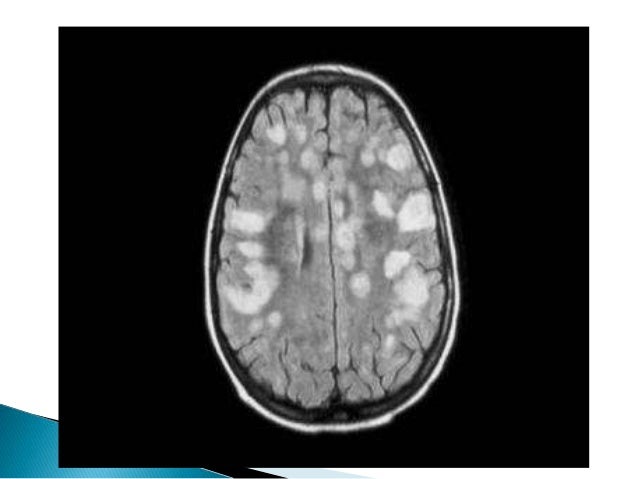

29. 29.  There are no diagnostic criteria, but ADEM must be suspected when one or more of the following are present :  •Initial multifocal presentation with multiple symptoms.  • Less than 10 years of age.  • Signs and symptoms of meningoencephalitis.  • Encephalopathy.  • Bilateral optic neuritis.  • CSF pleocytosis without oligoclonal banding.  • MRI shows lesions in areas not affected by MS, such as the grey matter or the cortex.  • Lesions on MRI appear larger with poorly defined edges that enhance with gadolinium

31. 31.  Polman et al. reviewed McDonald’s diagnostic criteria in 2010 and proposed the following :  Space: One or more lesions with and without gadolinium enhancement in two of the following areas:  periventricular,  juxtacortical,  infratentorial, or  spinal cord.  Time: One new lesion on T2 sequences or a gadolinium enhancing lesion when compared to the previous MR image, and concomitant finding of asymptomatic lesions with or without enhancement.

32. 32.  CSF oligoclonal bands (OCBs) are present in more than 90% of patients(may be absent after first attack)  Immunoglobulin (Ig)G index is seen in more than 60%. following equation: IgG Index -(CSF IgG/albumin)/(serum IgG/albumin). Ratio -0.3 and 0.6  Subclinical optic nerve involvement on visually evoked response testing  Advanced neuroimaging such as diffusion tensor and magnetization transfer imaging may help identify the involvement of the apparently normal white matter, which is abnormal in MS and normal in ADEM.

33. 33.  On the sagittal plane, the plaques may be anterior, central or posterior.  Acute lesions enhance with gadolinium, due to rupture of the blood-brain barrier. This enhancement is less in cerebral lesions.  Unlike neuromyelitis optica, viral or idiopathic myelitis, in MS no black holes are visualized in the spinal cord .  NAA has been has been found to be reduced on spectroscopy, in spinal cord areas that appear normal on conventional MRI.